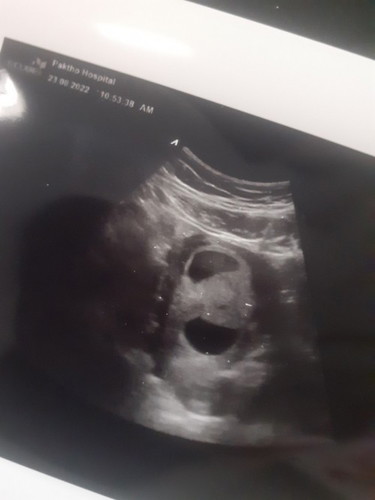

เเม่ๆค่ะดูยังไงหรอค่ะ ไม่เข้าใจ

หมอบอกว่าบอกไม่ได้ว่าอายุครรถ์เท่าไหร่ พอจะบอกได้มั้ยค่ะว่ากี่วีค

คุณแม่พอจะจำรอบเดือนครั้งสุดท้ายได้ไหมคะ แต่จริงๆอายุครรภ์มันจะขึ้นจอเลยนะคะว่าอายุครรภ์เท่าไหร่

น่าจะอายุครรภ์ยังน้อยอยู่นะคะแต่ภาพอัลตร้าซาวด์เหมือนท้องแฝดเลยคะ

เป็นตัวเเล้วค่ะเเม่ มีหัวเเล้วค่ะ

เหมือนเห็นถุงการตั้งครรภ์2ถุงนะคะแม่

แฝดไหมค่ะ

ไม่ค่ะคนเดียวจ้า